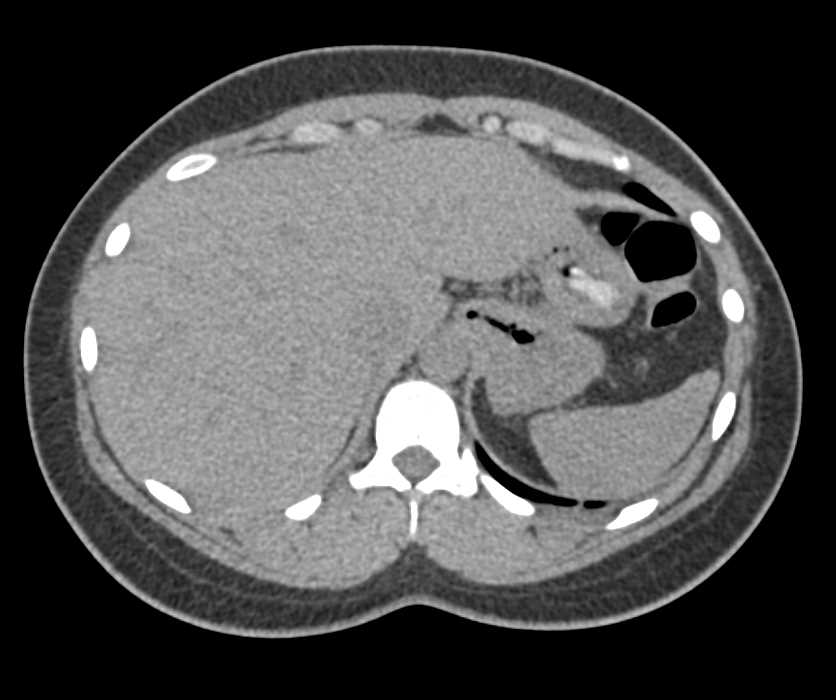

Retroperitoneal Fibrosis Encases the Aorta